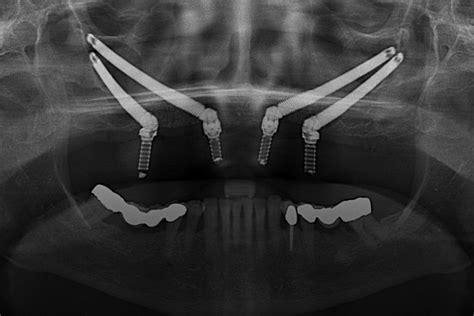

4. Implantes Cigomáticos

En pacientes con severa reabsorción maxilar, los implantes cigomáticos representan una alternativa efectiva sin necesidad de injertos óseos. Estos no tienen el mismo aspecto que los pernos de los que hablamos cuando describimos los implantes convencionales. Son mucho más largos.

«La gran idea de esta implantología alternativa fue diseñar unos nuevos implantes, más largos, que, recorriendo el seno maxilar, podían anclar un extremo en los pómulos. De esta manera, en el extremo contrario, que asoma en la encía, podemos colocar las prótesis. Con sólo cuatro implantes somos capaces de reconstruir todo un arco dental superior». Dr.

Los implantes cigomáticos se colocan directamente en el hueso del pómulo y están indicados en los casos en los que el paciente dispone de poco hueso o mala calidad del mismo.

- Planificación: Antes de la cirugía, el paciente se somete a una evaluación exhaustiva, que incluye tomografías computarizadas y modelos digitales en 3D para determinar la ubicación y el tamaño adecuado de los implantes.

- Procedimiento quirúrgico: La cirugía se realiza bajo anestesia general o sedación intravenosa. El cirujano hace pequeñas incisiones en las encías y coloca los implantes en los huesos cigomáticos. Una vez colocados los implantes, se coloca una prótesis provisional inmediata para que el paciente pueda sonreír y comer con normalidad.

- Prótesis final: Hecha a medida y ajustada perfectamente a la boca del paciente, restaurando la apariencia y función de los dientes naturales. Con la tecnología y los materiales avanzados de los que disponemos en la actualidad, las prótesis pueden verse y sentirse extremadamente realistas, lo que permite que los pacientes recuperen, por completo, su confianza y calidad de vida.